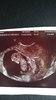

Wszystko w najlepszym porzadku.. wrecz idealnie! Pieknie sie rusza.. serduszko bez zarzutow..

Wydaje mi sie ze to chłopak jednak bedzie!